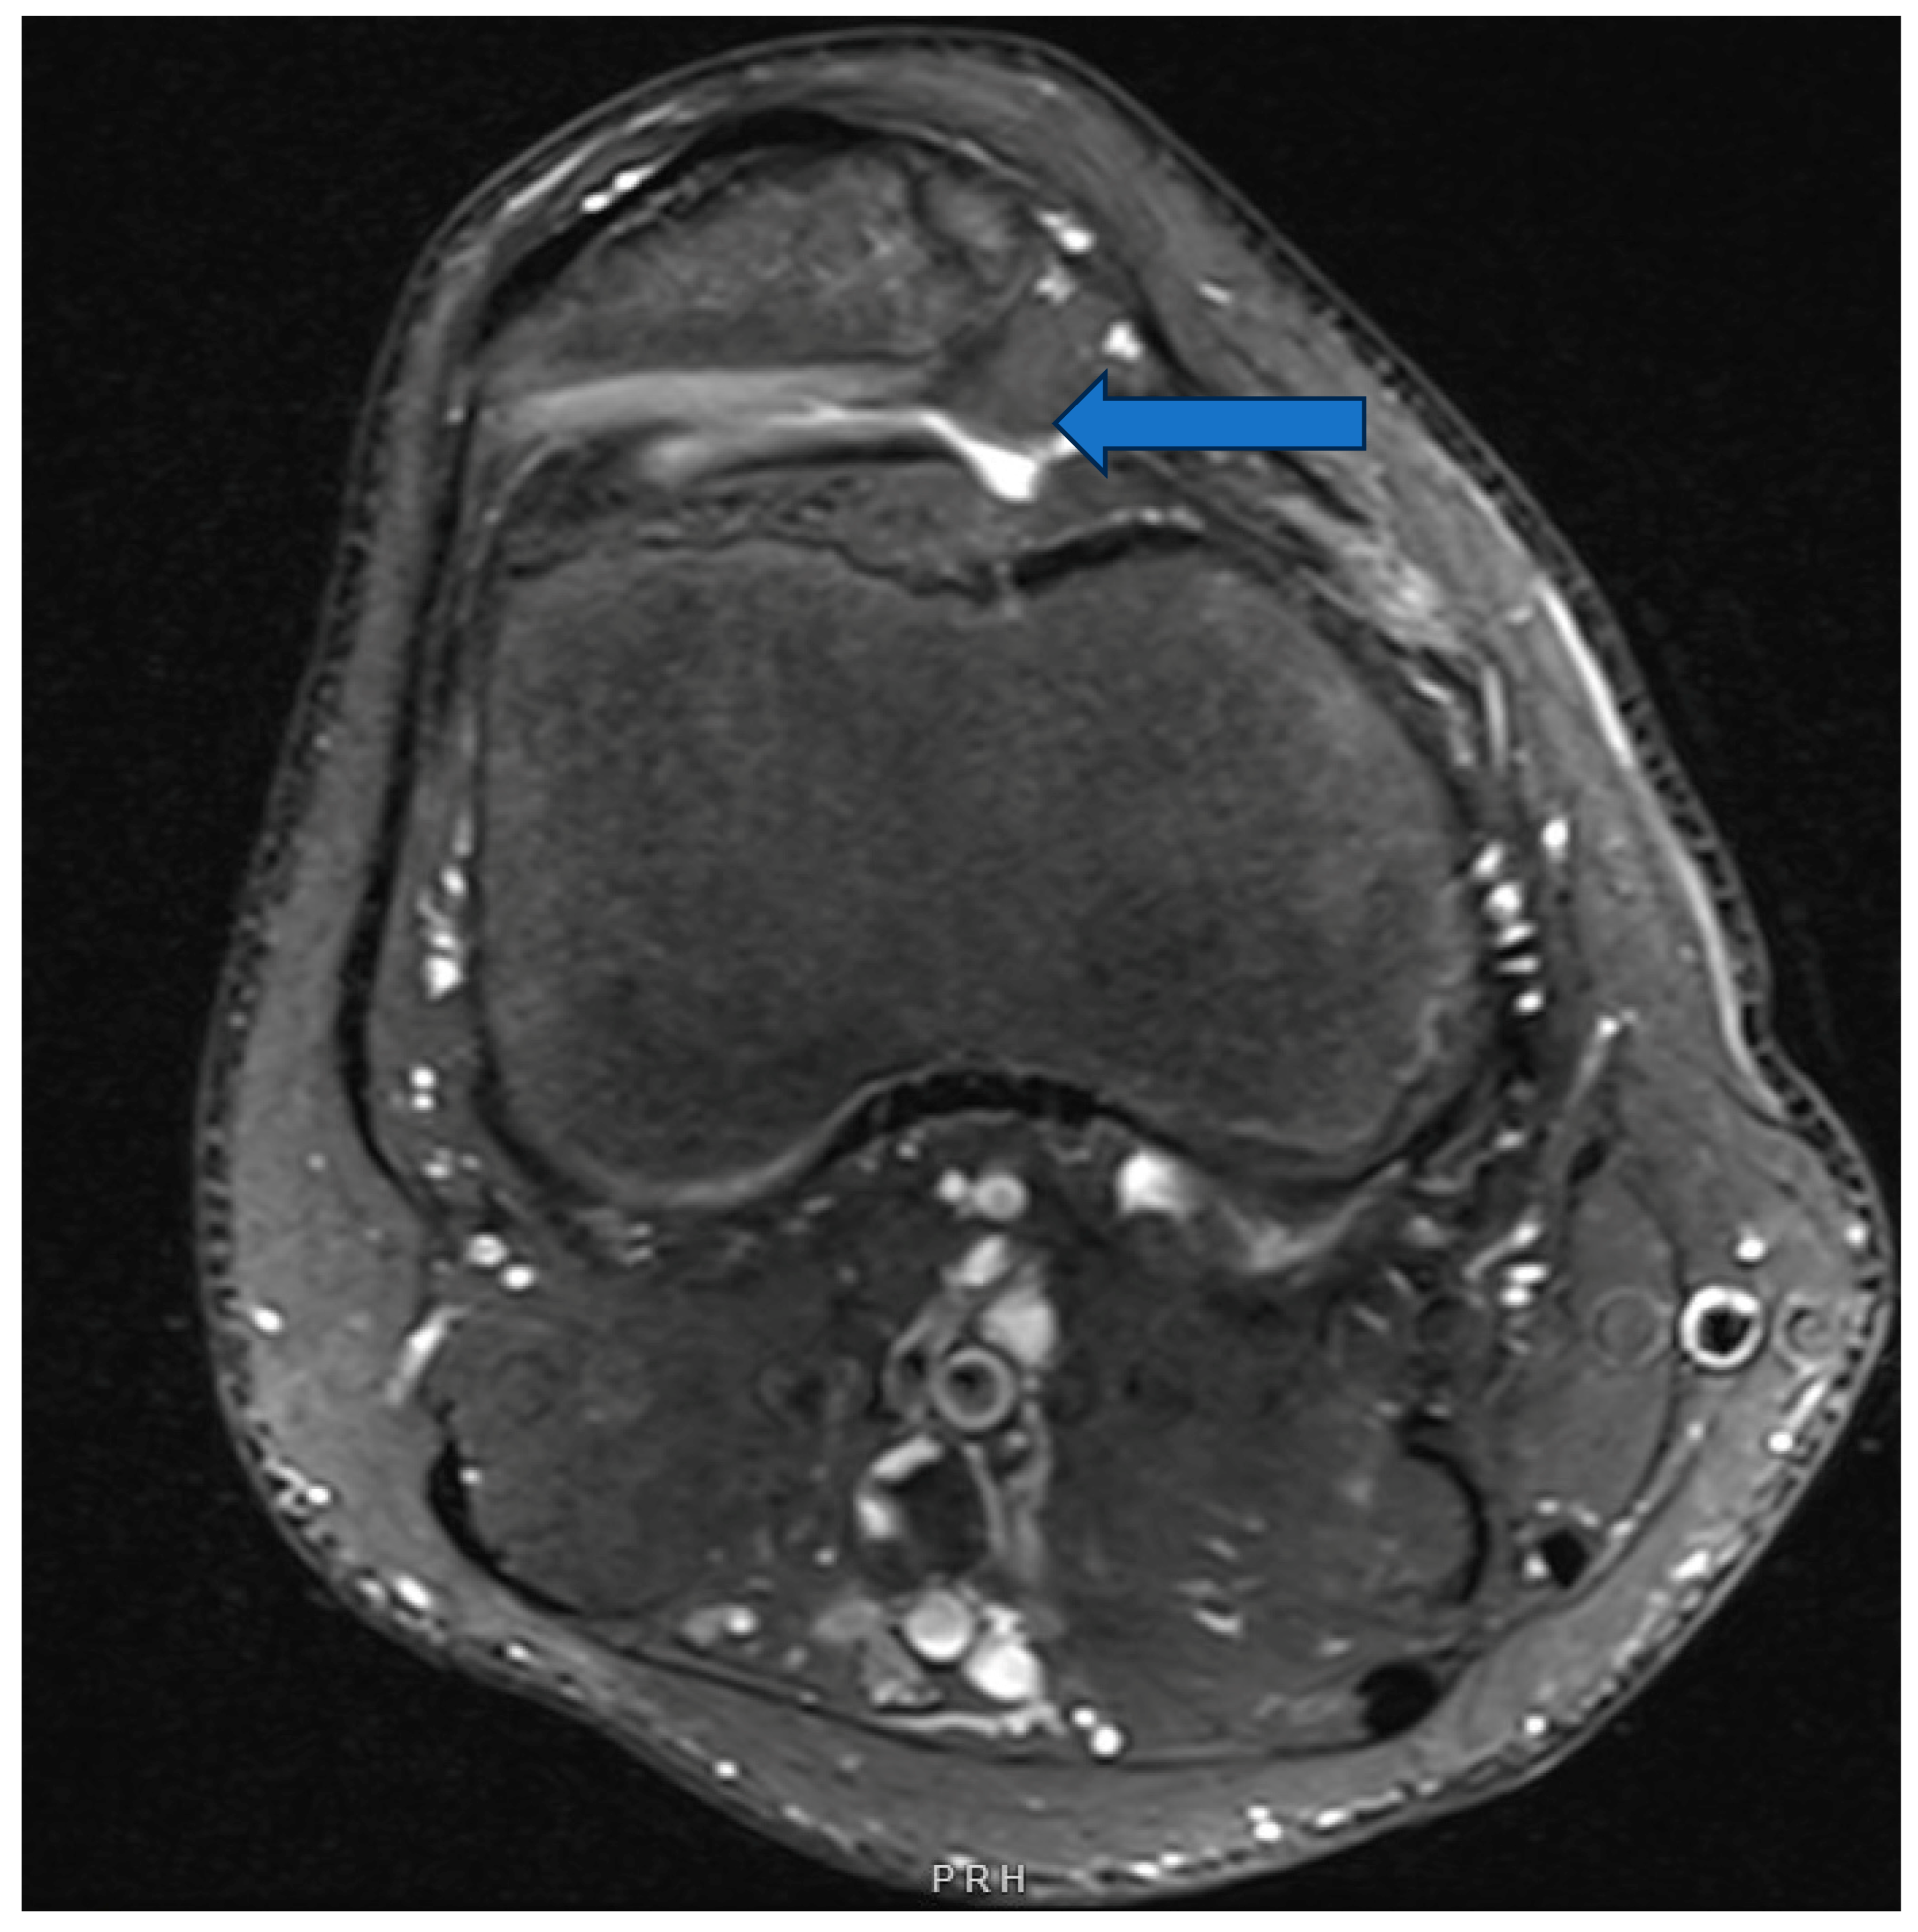

3.4. Elevated Tibial Tubercle to Trochlear Groove Distance (TT–TG)

8.2. Elevated Tibial Tubercle to Trochlear Groove Distance